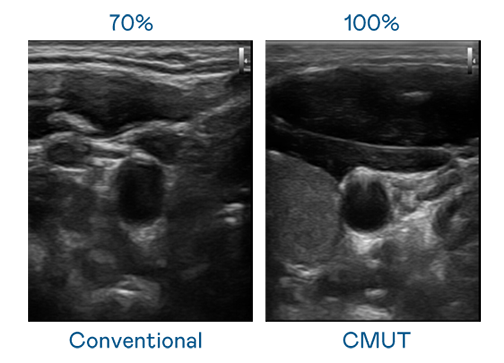

CMUT 技术是一种用电容式微机电元件来产生超音波讯号的技术。与传统 PZT 压电式技术相比,CMUT 频宽增加 30%,更宽频的超音波讯号让影像解析度大幅提升,是实现高影像品质医疗超音波扫描、促进精准医疗发展的关键技术。

超音波影像的解析度高低,首先取决于探头能发出的讯号频宽。人生就是博 CMUT 可提供高清晰的超音波讯号,提供高频宽、高灵敏度、影像纹理细节更高的超音波影像,协助医护人员缩短影像判读时间及利用精准的医疗影像进行诊断。